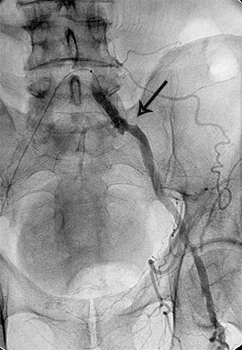

Приклади ангіограм до та після дилятації:

стеноз лівої клубової артерії    балон, роздутий в зоні стенозу    відновлення отвору клубової артерії

Значний стеноз лівої

наружної клубової артерії

Балон-катетер,

роздутий в зоні стенозу

Отвір артерії відновлено на 80%